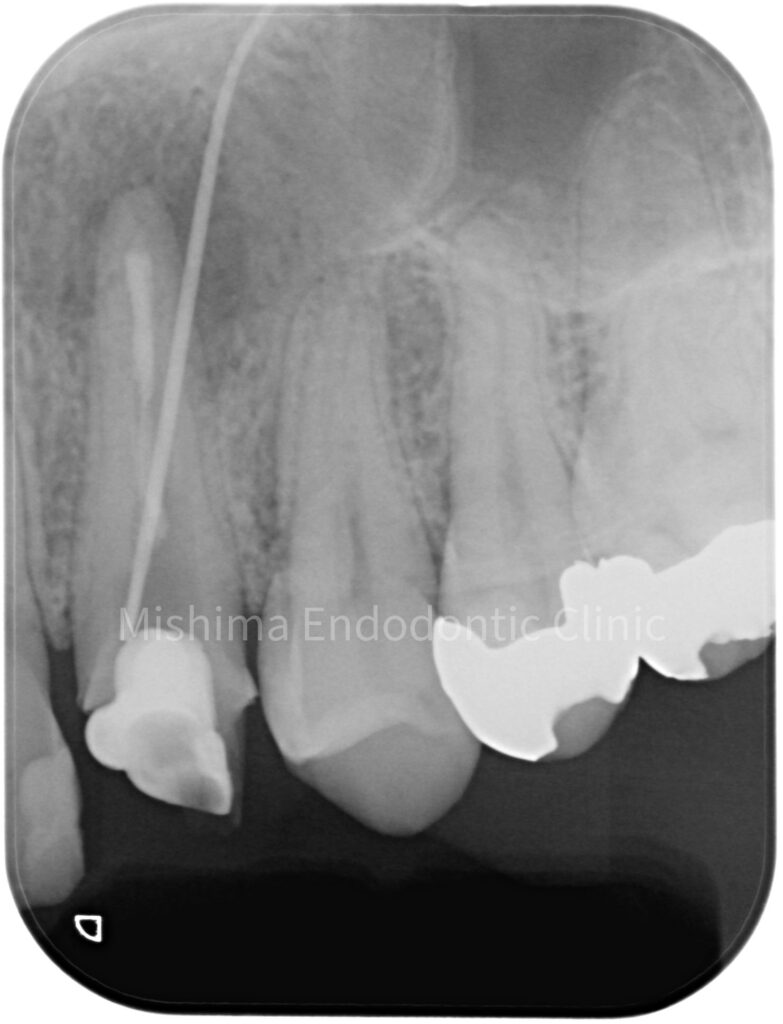

Before

| 主訴 | 根管治療を繰り返しているけど、痛みと腫れが引かない |

|---|---|

| 治療内容 | 23が既に根管治療が介入され仮封の状態で、サイナストラクト、自発痛を認めた。 根管治療を行うも症状の改善認めず、歯根端切除術へ移行。 |